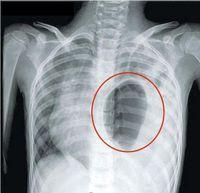

♥膈疝

>>膈疝概述

编辑词条 膈疝

主要症状:

腹痛,呕吐,呼吸困难,紫绀

所属科室:

外科 -

主要病因:

膈肌发育缺陷

发病部位:

胸腹部

多发群体:

婴幼儿